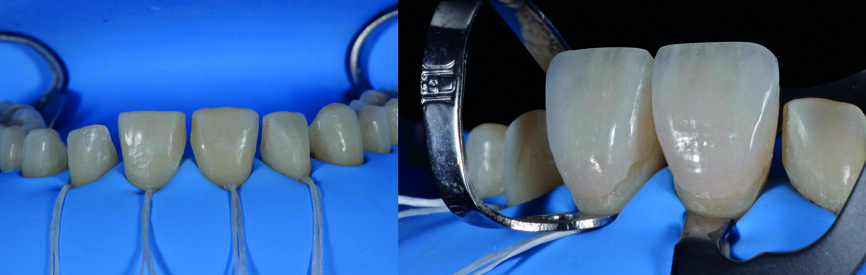

| Fig. 15a : Facettes en céramique feldspathique avec pâte d‘essai

Fig. 15b : Facettes réalisées en technique CFAO avec pâte d‘essai.

| Fig. 15c : Facettes en céramique feldspathique du premier quadrant et simultanément, facettes réalisées en technique CFAO du second quadrant avec pâte d‘essai.

Le jeu de facettes en céramique feldspathique a été fabriqué en IPS Style (Ivoclar Vivadent) sur un modèle en plâtre-pierre, tandis qu‘un bloc IPS Empress CAD Multi (Ivoclar Vivadent) a été utilisé pour le jeu numérique (Figs. 13 et 14). Les deux jeux ont été évalués en bouche avec une pâte d‘essai afin de comparer les propriétés optiques des facettes feldspathiques et des facettes réalisées en technique CFAO (Figs. 15a–c).

Le clinicien et la patiente ont décidé subjectivement un scellement des facettes en céramique feldspathique en raison des légères différences dans la longueur des incisives centrales des deux jeux. Les procédures adhésives ont suivi (Figs. 16a–f) et des photographies intra-orales et extraorales ont finalement été prises une semaine plus tard (Figs. 17a–e).